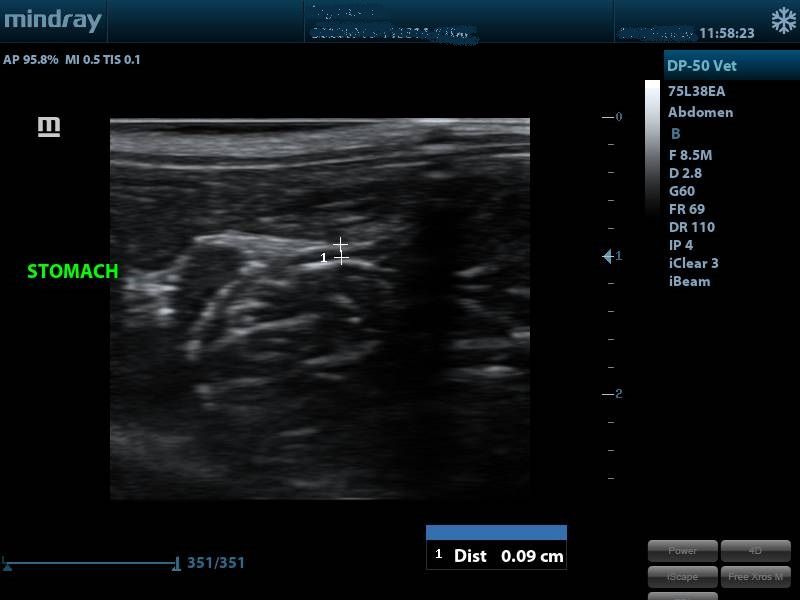

I have used this scanner in a few abdominal and cardiac cases as well as on Pippi . Overall I was pleased with the image I achieved for such a low budget machine.

I scanned with the microconvex probe and the linear probe. The linear probe gave good images at low depths and I used the microconvex probe for cardiac and abdominal cases which it managed reasonably well at.

Images from the Magic 6000 Plus / Mindray DP-50